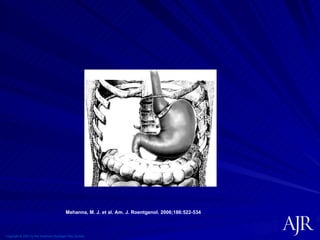

Copyright © 2007 by the American Roentgen Ray Society Mehanna, M. J. et al. Am. J. Roentgenol. 2006;186:522-534